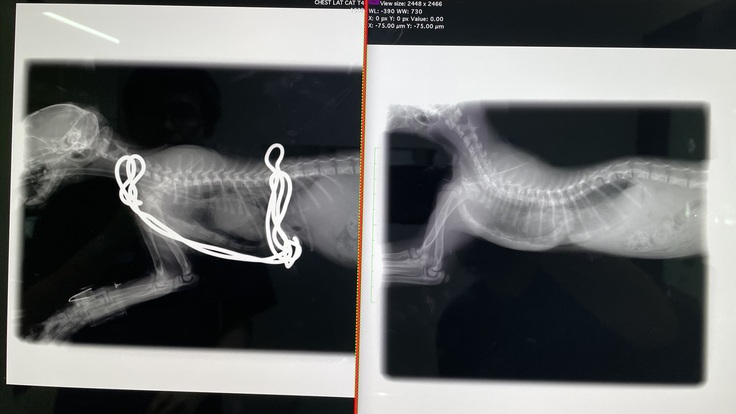

※写真 (左)after (右)before

思ってたより骨が変形していたそうで、肋骨の軟骨もすごい形をしていたそうです。歪んでいた心臓も術後はほぼ正常な位置に戻りました。

すごく骨が変形していた為、完全には綺麗な形にはならなかったみたいです。成長していくにつれて、少しずつコルセット(ギプス)を調整していき、様子を見ていく、とのことでした。